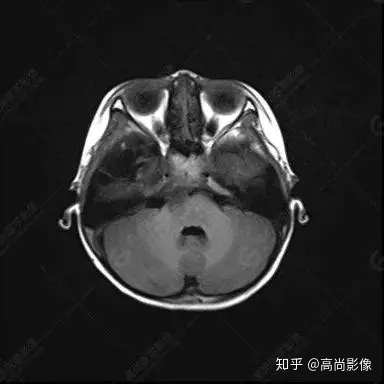

右側(cè)顳葉腫瘤切除術(shù)后(具體不詳):右側(cè)顳部骨質(zhì)不連續(xù)呈術(shù)后改變,右側(cè)顳葉術(shù)區(qū)見片狀長T1長T2信號影,F(xiàn)LAIR呈低信號;術(shù)區(qū)后方右側(cè)顳枕葉見一巨大占位性病變影,邊界欠清,大小約6.2×5.8×4.3cm(前后×左右×上下),信號不均勻,T1WI呈等稍低信號間雜少許高信號,T2WI呈高稍低混雜信號,DWI示部分病灶彌散受限,相應(yīng)ADC圖減低,磁敏感序列見部分呈極低信號,增強(qiáng)掃描可見明顯不均勻強(qiáng)化,鄰近硬腦膜及小腦幕增厚并明顯強(qiáng)化;另延髓右前方及右側(cè)橋小腦角區(qū)見一不規(guī)則形異常信號影,大小約3.2×1.3×3.7cm(左右×前后×上下),呈長T1稍長T2信號,F(xiàn)LAIR呈等信號,DWI未見受限,增強(qiáng)后明顯均勻強(qiáng)化,鄰近腦膜明顯強(qiáng)化。鄰近腦實質(zhì)及右側(cè)顳角明顯受壓;左側(cè)大腦半球未見局灶性信號異常,中線結(jié)構(gòu)稍左移。

右側(cè)顳葉腫瘤切除術(shù)后:現(xiàn)術(shù)區(qū)后方右側(cè)顳枕葉及延髓右前方占位,右側(cè)顳枕部硬腦膜及小腦幕明顯強(qiáng)化,結(jié)合既往影像資料,考慮為胚胎源性惡性腫瘤,如非典型畸胎樣/橫紋肌樣瘤(AT/RT)或原始神經(jīng)外胚層腫瘤(PNET)。

非典型畸胎樣/橫紋肌樣瘤(AT/RT) 是一種高度惡性中樞神經(jīng)系統(tǒng)腫瘤,臨床罕見,臨床表現(xiàn)無特異性,好發(fā)于 5 歲以下兒童,尤以 3 歲以下多見,在兒童原發(fā)性中樞神經(jīng)系統(tǒng)(CNS)腫瘤中占 1%~3%。該腫瘤體積一般較大,幕上大于幕下,有明顯的占位效應(yīng)。該腫瘤成分復(fù)雜,囊變、出血、壞死常見。因此 AT/RT信號混雜,囊性部分呈 T1WI低、T2WI高信號,增強(qiáng)后不強(qiáng)化;若瘤體出血,囊內(nèi)可見T1WI稍高信號、T2WI低信號,實性部分在 T1WI上呈混雜等、低信號,在T2WI 及 T2-FLAIR上呈混雜等高信號,增強(qiáng)掃描后大部分呈環(huán)形條帶樣明顯強(qiáng)化,中心壞死區(qū)不強(qiáng)化。另外,該腫瘤實性成分在DWI上呈高信號,說明腫瘤細(xì)胞核密集,水分子擴(kuò)散明顯受限,提示該腫瘤惡性程度高,容易復(fù)發(fā)及轉(zhuǎn)移。